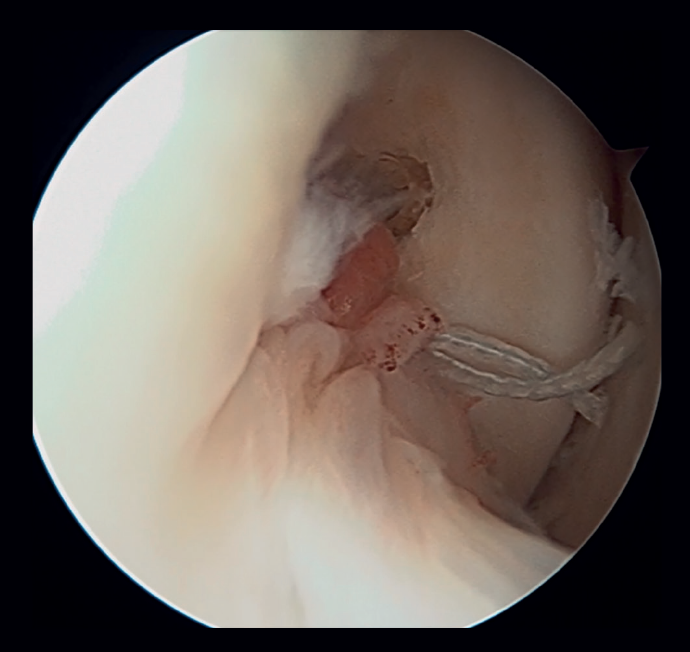

La principal indicación es la rotura del fascículo superior del LTFA de su inserción fibular presentando una buena calidad tisular del remanente de ligamento (Figuras 1 y 2).

Figura 1. Identificación de la inserción fibular del ligamento talofibular anterior con excelente calidad del remanente tisular. Técnica con 2 implantes sin nudos y a través de un portal único modificado.